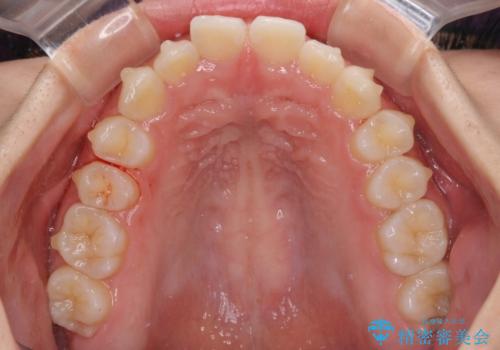

前歯のデコボコと突出感 インビザラインによる矯正治療

- 上下前歯のデコボコと、上顎前歯の突出感を気にして来院された患者様です。

インビザラインによる上下歯列の側方拡大と後方移動、IPR(歯と歯の間を削る)にるスペースの獲得により歯列を整えることとしました。

毎日22時間以上しっかりとマウスピースを装着していただいたので、スムーズに治療が進みました。歯と歯の間を削ることでうまくスペースコントロールでき、1年強で終えることができました。